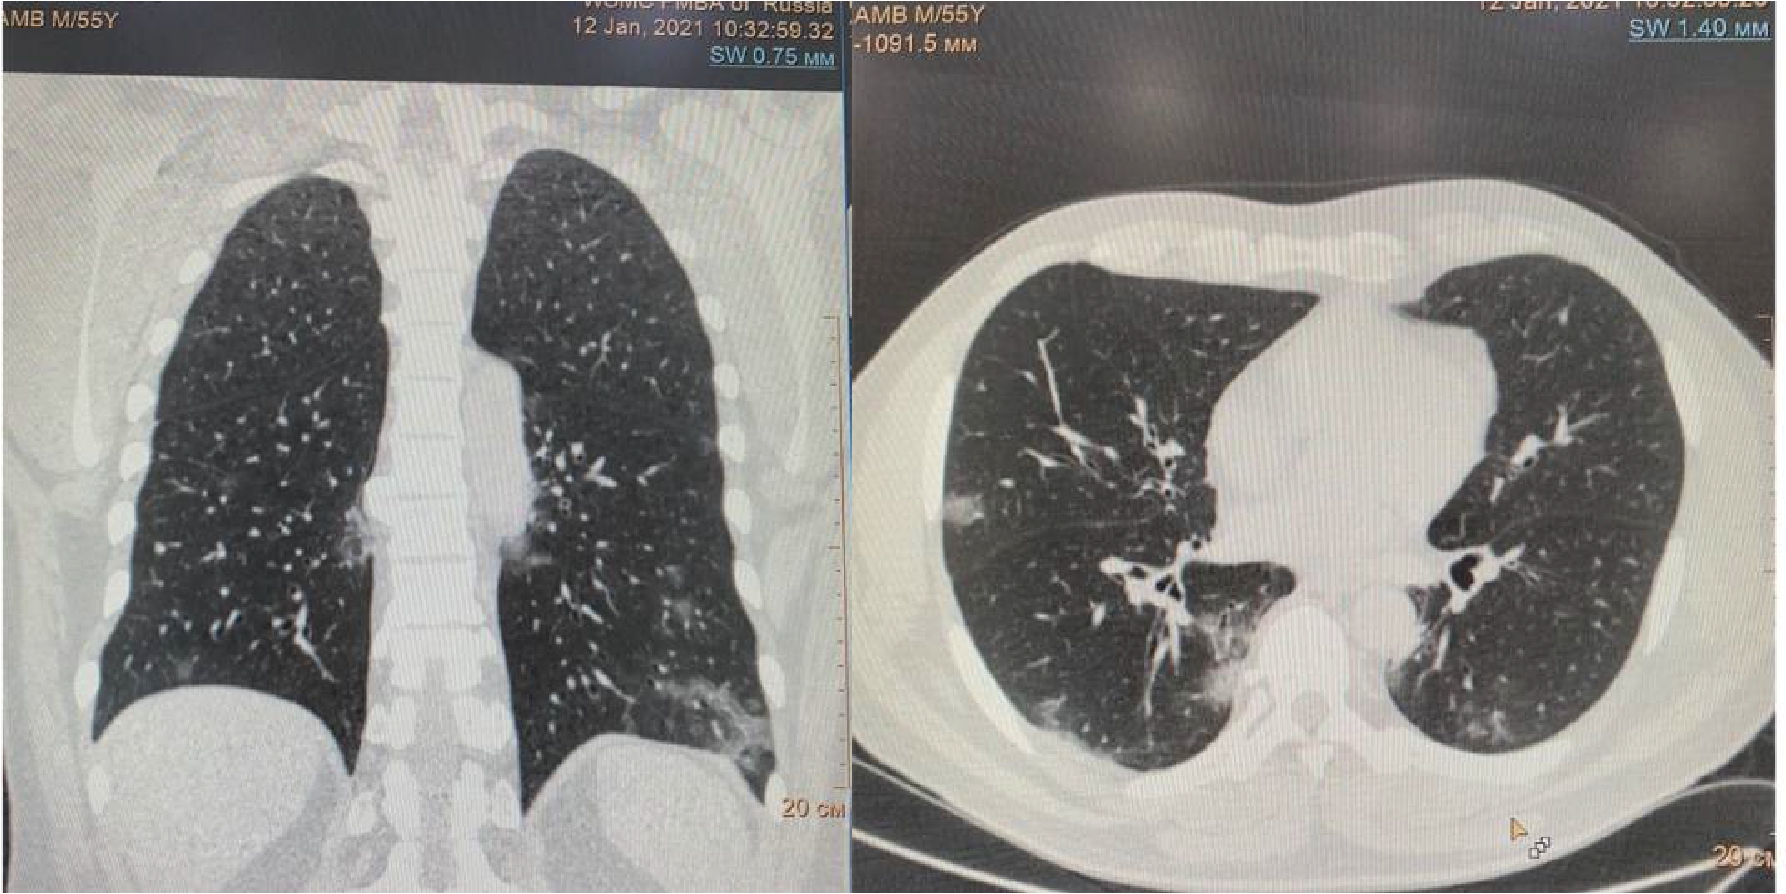

Проведено дренирование плевральной полости справа по Бюлау. В результате отмечена отчетливая положительная динамика в виде устранения одышки, повышения SpO2. Через 3-е суток при контрольной рентгенографии органов грудной клетки выявлен верхушечный пневмоторакс справа (рис. 6), проведена пункция плевральной полости, дренирование продолжено. На фоне устойчивой положительной динамики в дальнейшем, на 23-е сутки терапии пациент выписан в удовлетворительном состоянии.

Рисунок 6. Рентгенограмма органов грудной клетки – признаки двусторонней полисегментарной интерстициальной пневмонии (объем поражения 30%, КТ-2). Верхушечный правосторонний пневмоторакс